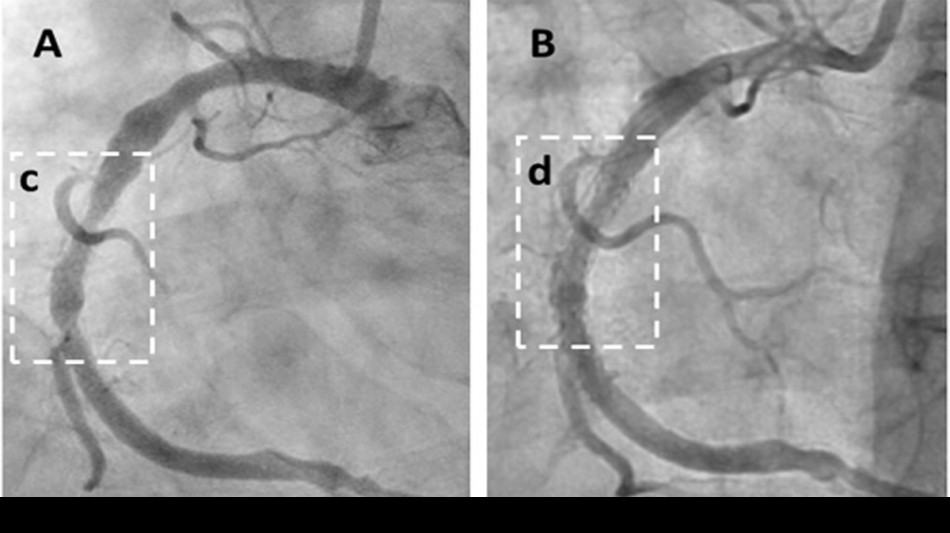

Angiogram: Plaque Reduced Within 6 Weeks

The peer-reviewed case series demonstrates rapid symptom relief and significant regression of arterial plaque, marking a potential paradigm shift in heart disease treatment. The study followed 20 high-risk patients with advanced angina, with 18 (90%) reporting substantial symptom improvement (P0.0001) compared to expected outcomes. Objective imaging confirmed unprecedented results, including Coronary Artery Calcium (CAC) score reductions (e.g., from 591 to 521) and a 70% coronary artery blockage reduced to 27%. Cavadex, formulated with 2-hydroxypropyl-β-cyclodextrin (HPβCD), stimulates the body's natural vascular repair, offering a faster, more effective approach than existing therapies.